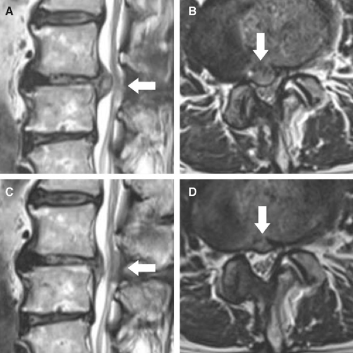

요추 (허리) 디스크의 비수술적 치료법으로 TELA라고 하며 정식 명칭은 추간공 경막외 레이저 디스크 성형술 입니다. (transforaminal epiduroscopic laser annuloplasty) 주사를 하듯 환자의 허리로 접근하여 척추에서 신경이 나오는 추간공을 통해 척추관 내에 돌출 된 디스크의 크기를 레이저를 이용하여 감소 시킵니다.

척추관 내시경 처럼 레이저를 이용하여 돌출 된 디스크의 크기를 줄이지만 꼬리뼈가 아닌 추간공 (허리) 을 통해 척추관으로 접근하게 됩니다. 허리를 통해 시술을 위해 설계 된 전용 삽입관을 피부에서 척추까지 길게 삽입하여 내부에 설치 된 내시경을 통해 병변을 확인하고 레이저 카테터를 삽입하여 디스크의 크기를 줄입니다. C-arm을 이용하여 정확도와 안전성을 높이게 됩니다. 척추관 내시경으로 접근이 어려운 척추 가쪽관의 디스크 돌출 병변에 좀 더 쉽게 접근이 가능하며 전신 마취 없이 국소 마취만으로 시술 진행이 가능 합니다.